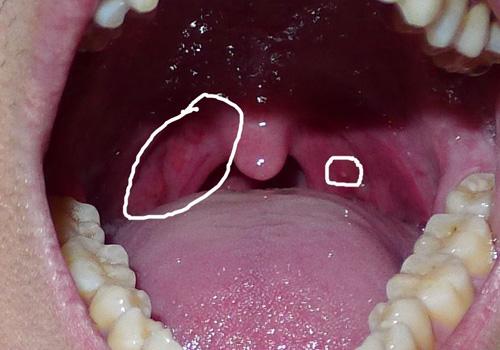

求救,感冒引起的,咽喉一致很痛,帮我看看出了什么症状?

喉咙里长了这些水泡样的东西不知道是什么,早上刷牙会恶心干呕,有时

嗓子上有疙瘩,老是反复复发,又快2年了,怎么回事?